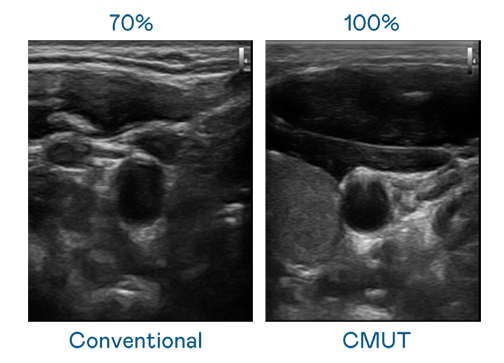

CMUT 技術是一種用電容式微機電元件來產生超音波訊號的技術。與傳統 PZT 壓電式技術相比,CMUT 頻寬增加 30%,更寬頻的超音波訊號讓影像解析度大幅提升,是實現高影像品質醫療超音波掃描、促進精準醫療發展的關鍵技術。

超音波影像的解析度高低,首先取決於探頭能發出的訊號頻寬。97国际 CMUT 可提供高清晰的超音波訊號,提供高頻寬、高靈敏度、影像紋理細節更高的超音波影像,協助醫護人員縮短影像判讀時間及利用精準的醫療影像進行診斷。